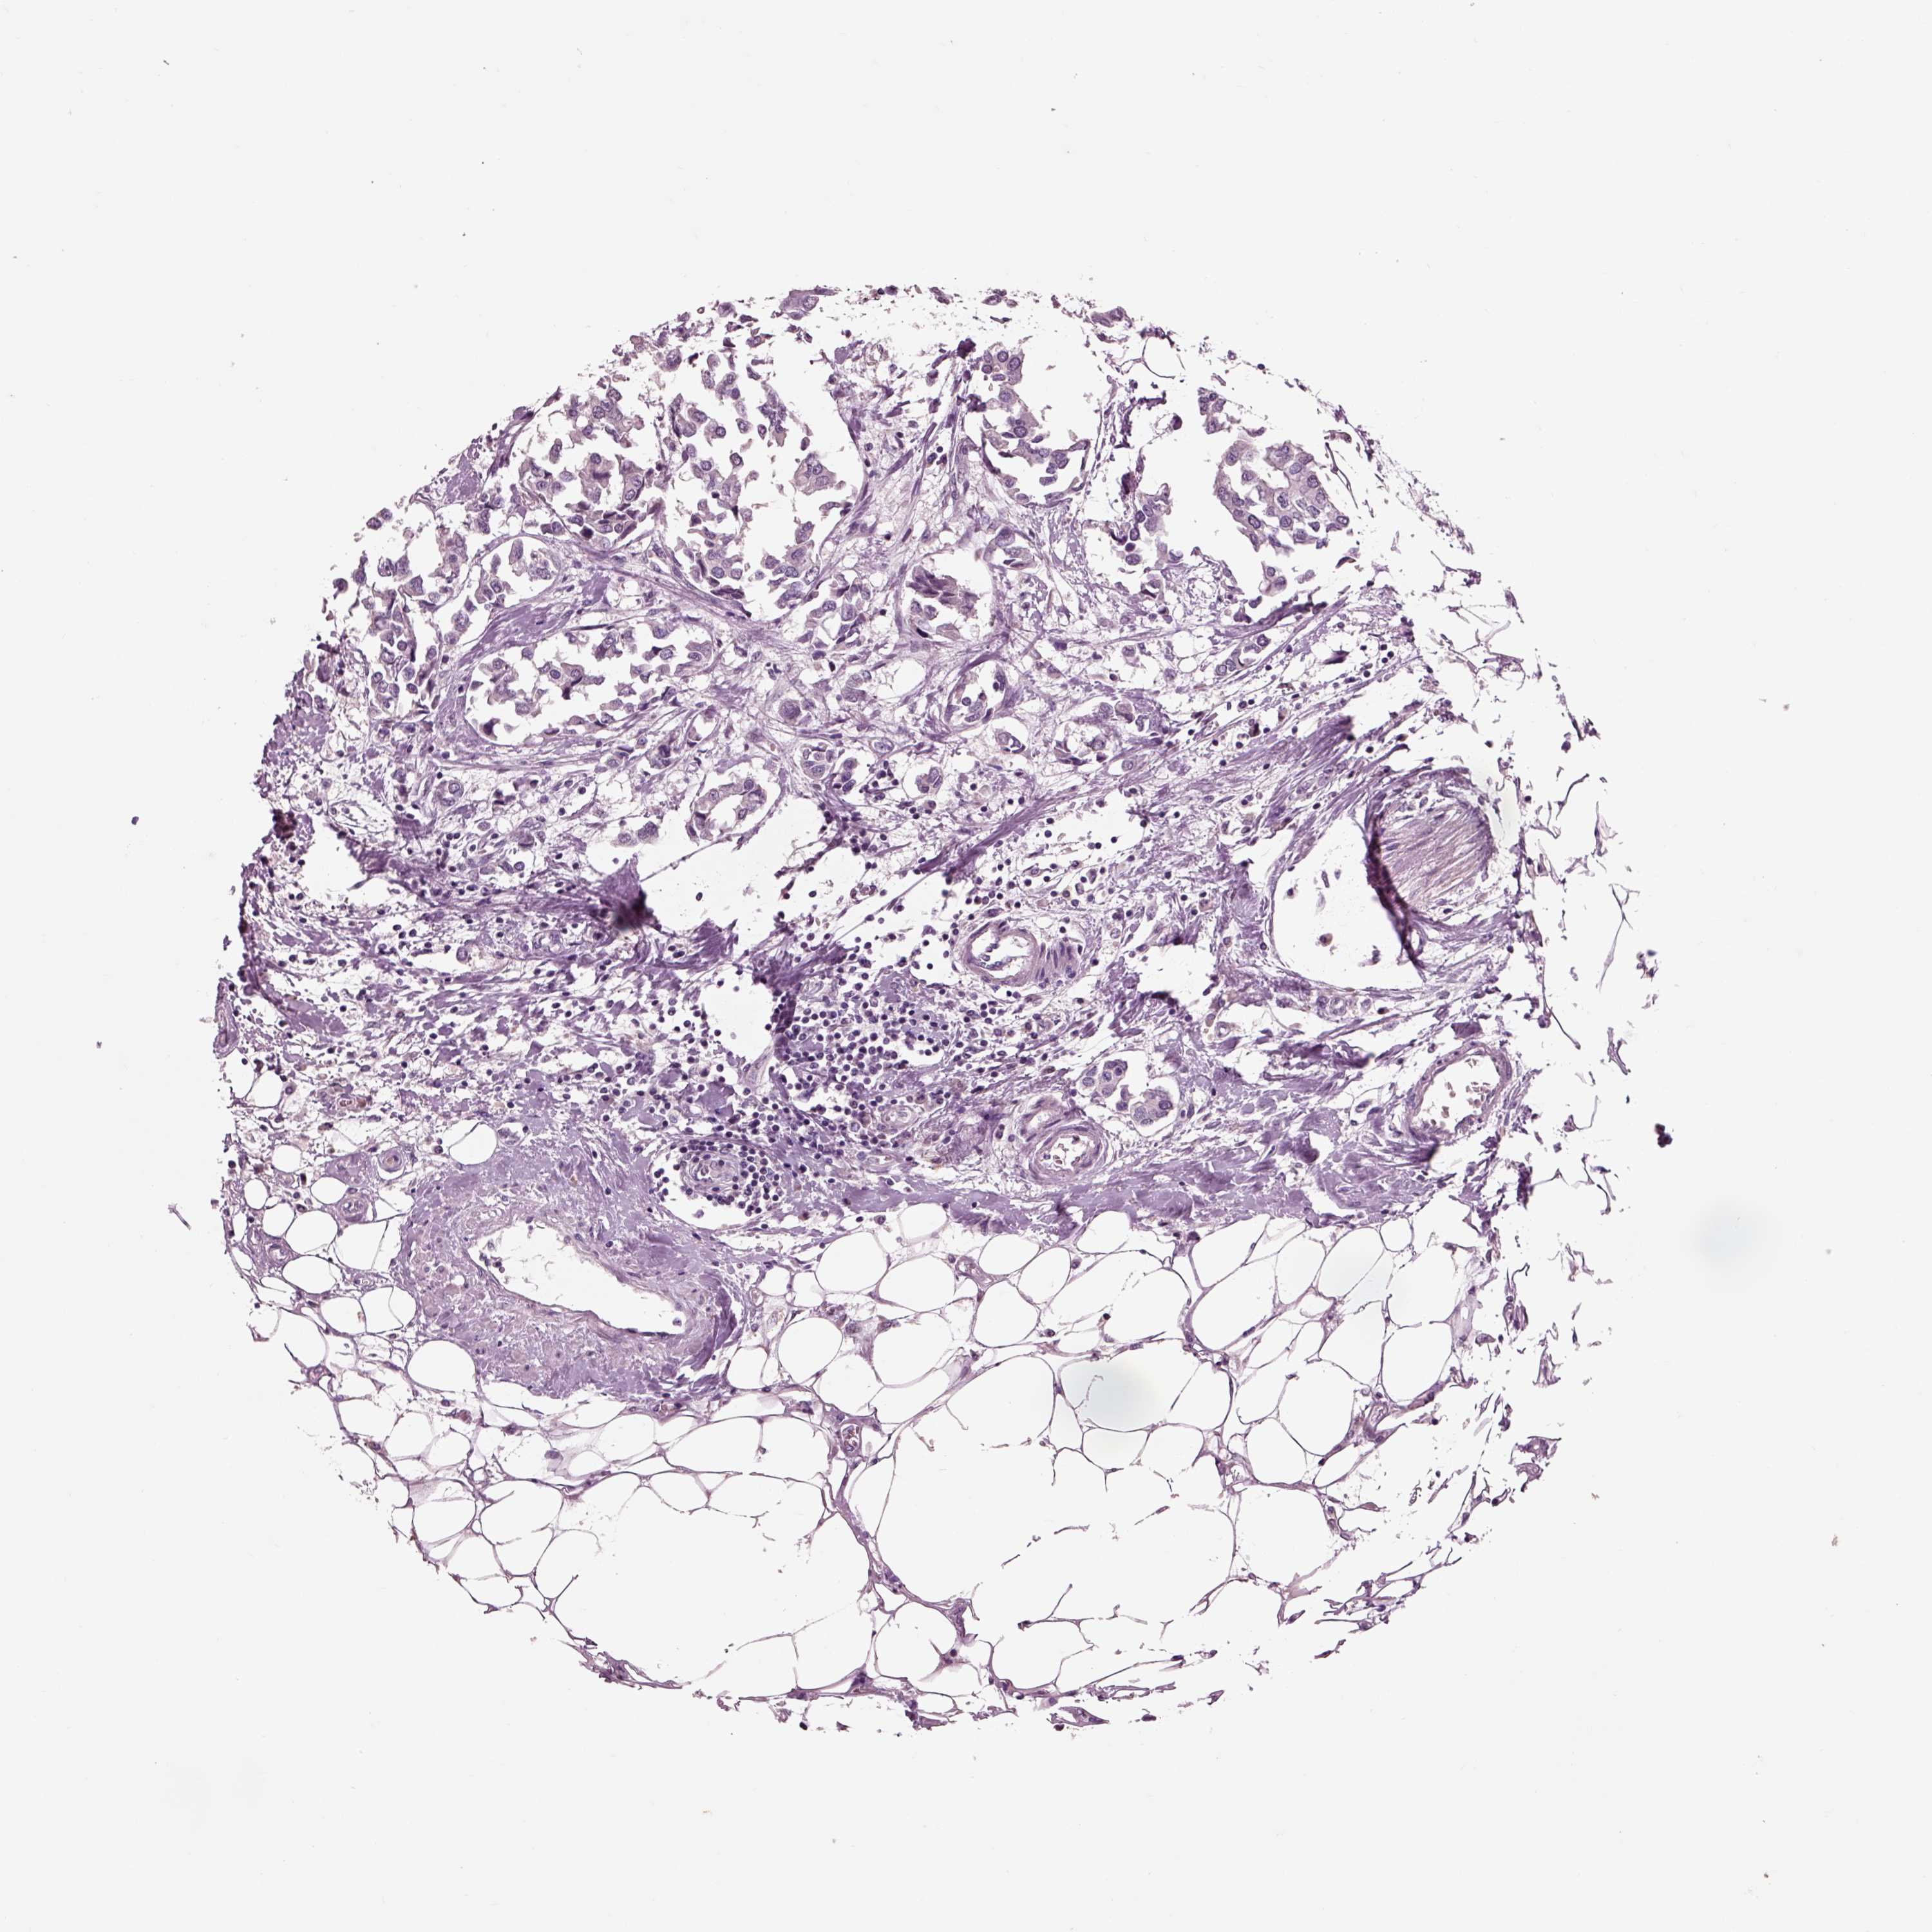

Breast cancer

Human cancer